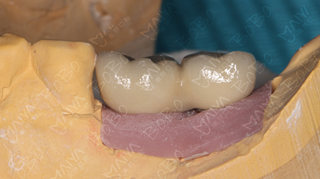

种植完成后的牙齿情况